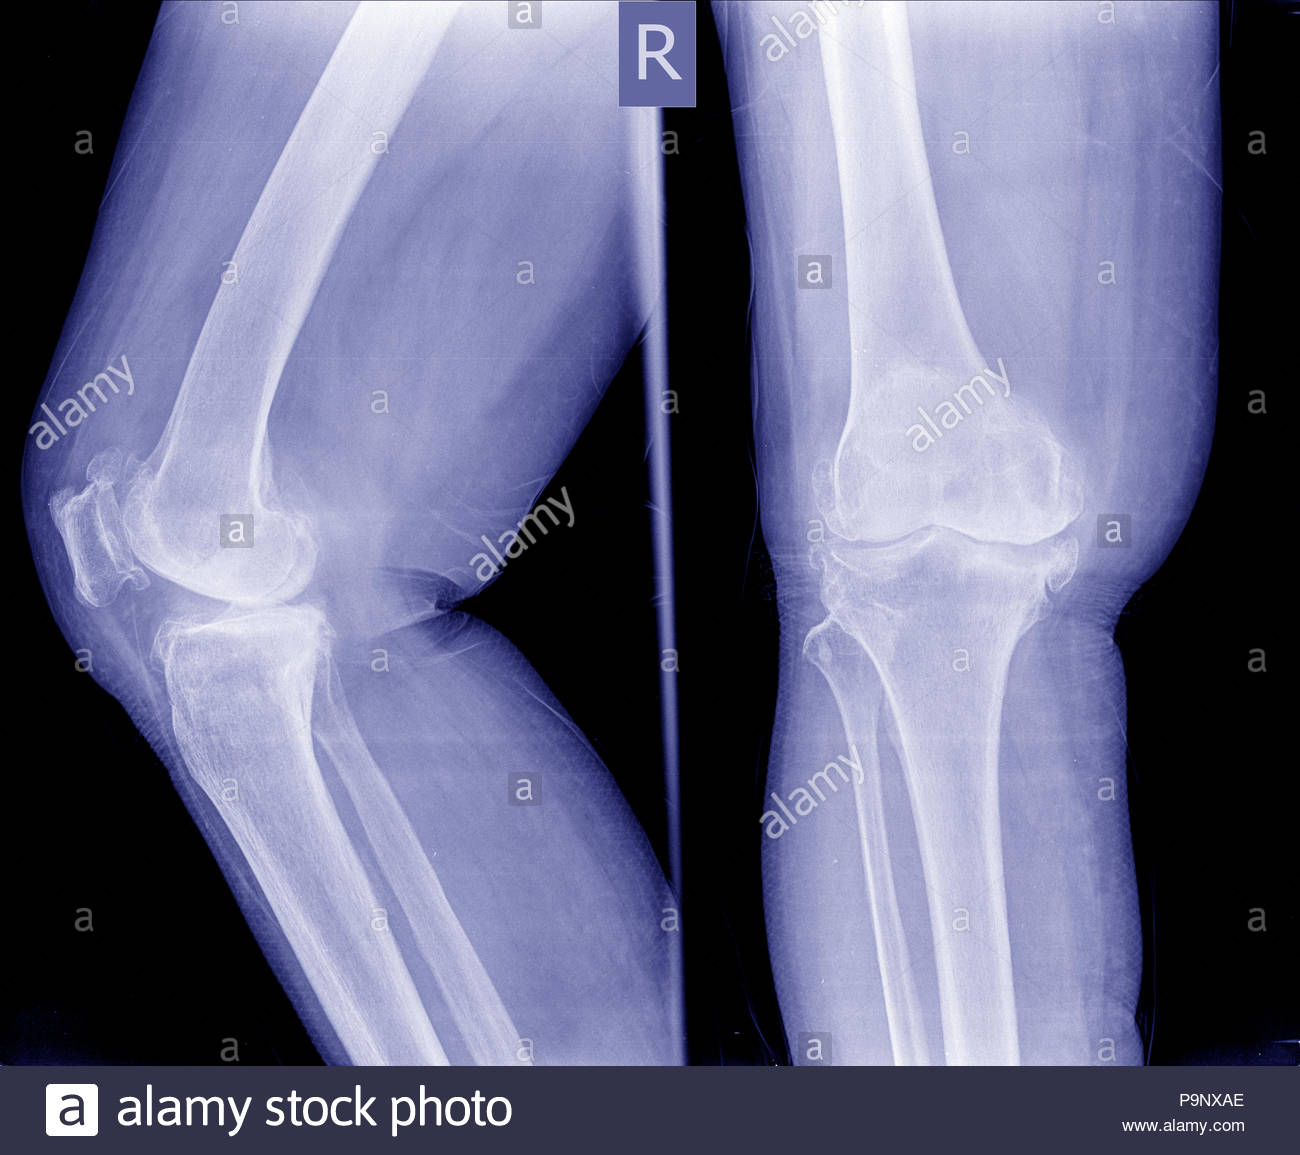

Osteoarthritis knee . film xray knee ( anterior posterior and Whats A Knee Spur Learn what bone spurs in the knee are, how they form, and how they affect your joint health. Presenting as bony lumps, they tend to be more prevalent in patients over 60. Bone spurs in the knees are a relatively common contributor to knee pain with movement, like walking, standing, and bending. Bone spurs are bony growths that form along. Whats A Knee Spur.

Osteoarthritis Both Knee . Film Xray AP Anterior Posterior of Knee Whats A Knee Spur Learn what bone spurs in the knee are, how they form, and how they affect your joint health. Bone spurs are bony growths that form along bone edges, often due to osteoarthritis. They can cause pain, nerve irritation or movement issues, and may. They can cause pain, stiffness and nerve compression, and may require. They can cause pain and loss. Whats A Knee Spur.